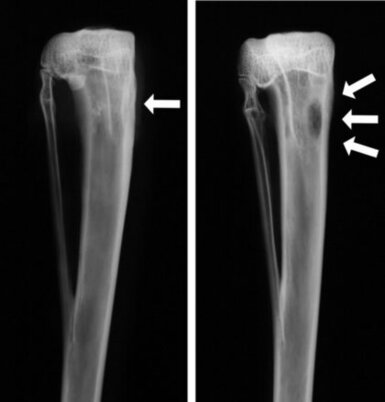

Современное оборудование для аппаратной диагностики позволяет определить степень разрушения кости, наличие гнойных ходов, их расположение. Для этого назначают рентгенографию, компьютерную томографию, магнитно-резонансную томографию, сцинтиграфию, денситометрию, УЗИ и другие методы. Чтобы правильно выбрать антибактериальный препарат, необходимо обследовать гнойное содержимое на возбудителей.

Обследование остеомиелита производится путем таких лабораторно-инструментальных способов исследования:

• фистулография с введением контрастного вещества;

• КТ или МРТ;

• рентгенограмма;

• общий анализ крови.

При необходимости применяется радиоизотопное сканирование, пункция костномозгового канала, биопсия костного мозга.